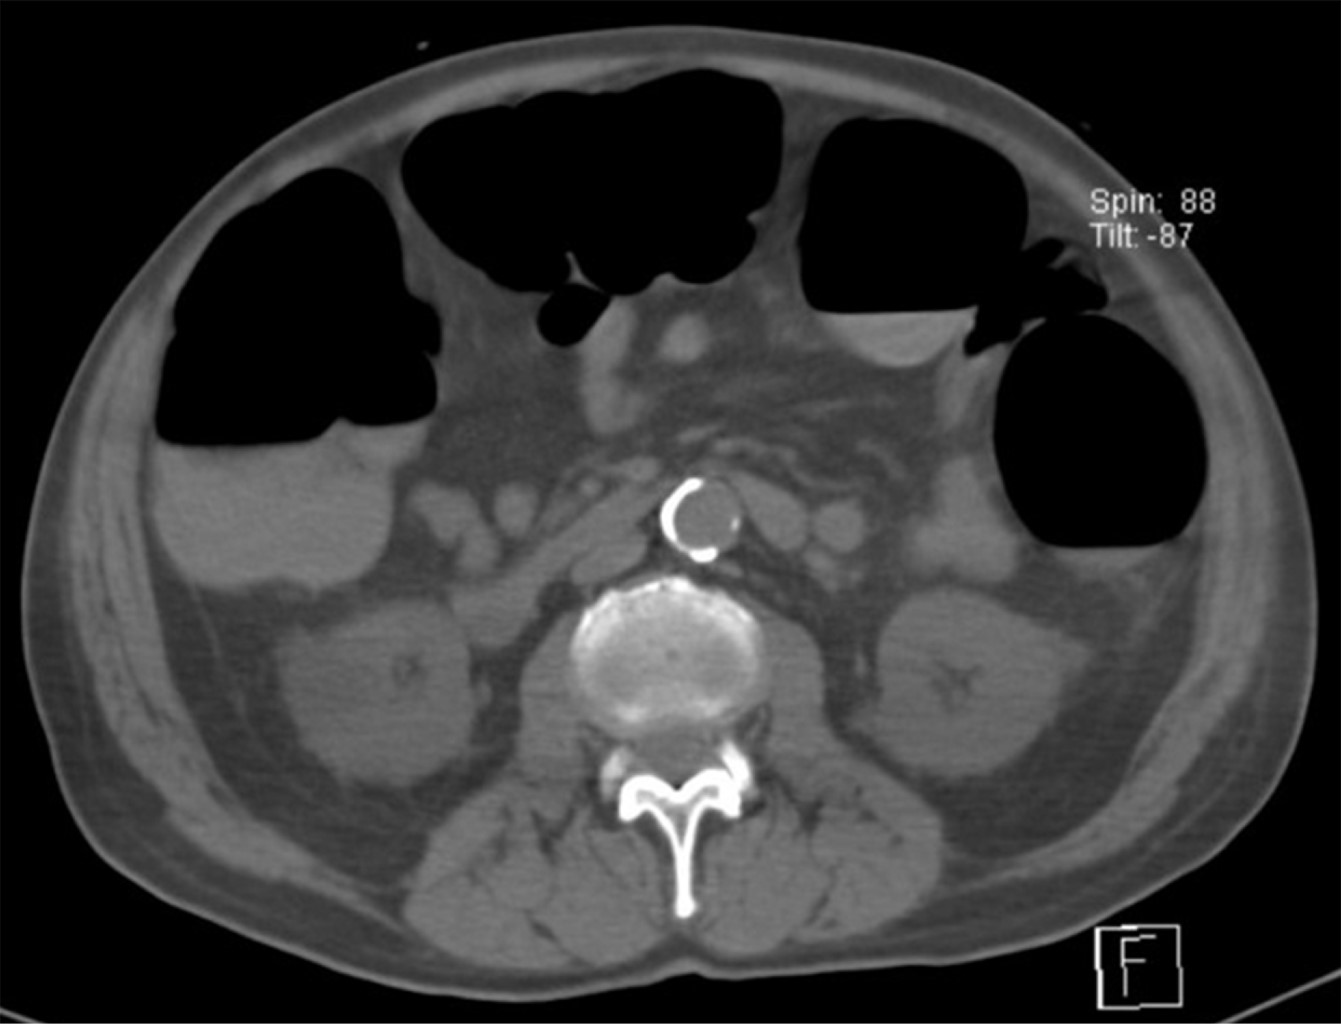

Ogilvie´s syndrome, acute colonic pseudo-obstruction; report of a case in Mexico

Ogilvie's syndrome or acute colonic pseudo-obstruction is a rare entity resulting from a loss of coherence between the sympathetic and parasympathetic activity of the colon, resulting in a mortality rate of up to 50%, debuting as a spontaneous perforation, increasing the risk of death. in the delay in diagnosis and decision making; The most frequent causes are cerebral vascular event, pathological postpartum acute myocardial infarction and sepsis. We present a case report of a 73-year-old male patient, who attended the emergency department for a hemorrhagic cerebrovascular event of aneurysmal etiology, which led to a prolonged hospital stay of 9 days with abdominal distension. refractory to conservative management, with surgical resolution documenting acute colonic pseudo-obstruction. We emphasize the importance of the etiological suspicion, as it is a diagnosis of exclusion, to reduce the complications derived from an untimely surgical act, increasing days of hospital stay and mortality.

Figure 1

Figure 2

Figure 3

Figure 4